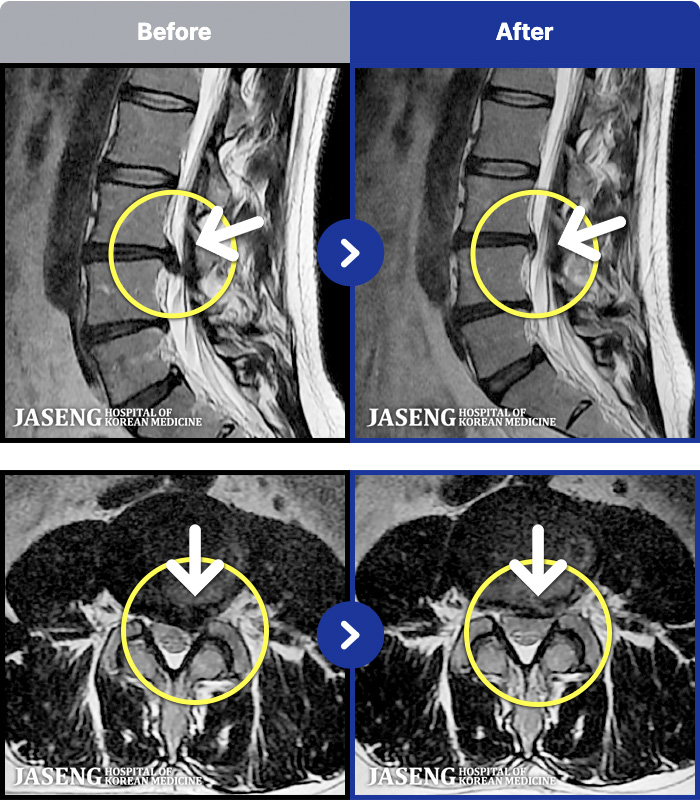

[Կñ:20.12.18~24.11.15]

[_㸮ũ] 㸮 Ұ. ٸ , ȭŸ Ÿ

No.46

ȸ 576

2024.12.24